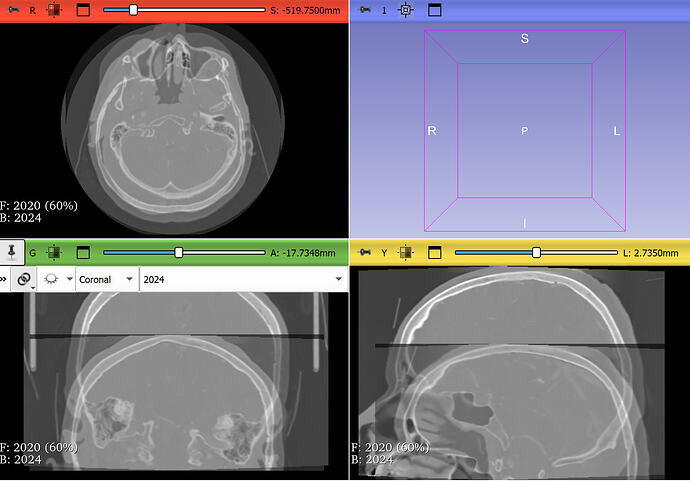

my goal is to register CTA Circle of Willis examinations of two patients acquired with a 4-year interval, using the skull as a reference, in order to evaluate changes in the position of the arterial tree over time.

Your images have several strange properties, any of them may can cause an automatic intensity-base image registration methods to struggle:

• Most registration methods generally require the images cover the same region. Your images do not meet this requirement. To fix this, probably the easiest is to crop the images to approximately to the same region.

• Image intensity range is off. Most medical images are in the range of +/- few thousand, while yours are in few ten thousands. This may result in default registration presets not working ideally on the images.